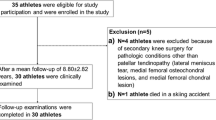

A total of 14 PTR reconstructions were performed in the aforementioned time frame. Four patients also suffered concomitant ligamentous knee injuries and two patients had secondary contralateral PTR and were therefore excluded. Of the remaining 8 patients that were eligible for inclusion, 7 (87.5%) participated in the physical examination and strength assessment. One patient did not consent to participate and was therefore excluded. Of those 7 PTR, 3 occurred during ball sports (1 × basketball, 1 × handball, 1 × soccer), 2 occurred during winter sports (1 × alpine skiing, 1 × snowboarding), and one each occurred during a motorcycling and skateboarding accident. The median follow-up was 17.0 (16.0–77.0) months. The patients’ demographics are shown in Table 1.